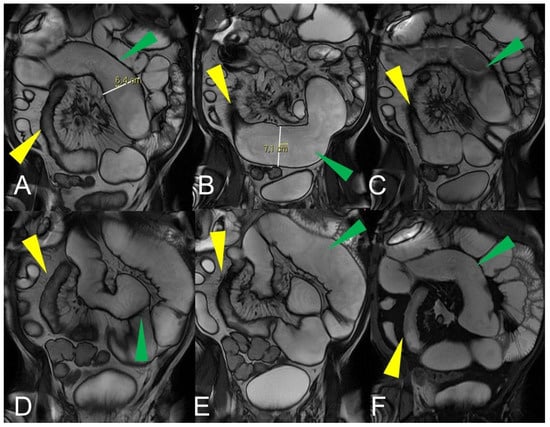

An abdominal phlegmon is an obsolete term that refers to an inflammatory mass that can develop in the setting of penetrating Crohn’s disease. The term phlegmon is ambiguous and relates to an ill-defined inflammatory dense mesenteric mass. It typically spreads without a well-defined wall and involves the mesentery and adjacent bowel with fistula or abscess as possible complication [12]. Inflammatory conglomerate is the accurate terminology to use in the radiological reports. On MRE images, it appears as a variable signal intensity mixed with fat, usually associated with signs of penetrating disease such as complex fistulas [5] (Figure 12, Figure 13 and Figure 14).

Figure 12.

Inflammatory conglomerate represents a climbing mesenteric fat involvement in the context of penetrating disease and mesenteric inflammation. The components of the fistulas within the mass can be difficult to detect because it often coexists with phenomena of retraction that are expressed on the intestinal loops nearby or on the ureters. Small inflammatory conglomerate in the context of the mesentery adherent to a segment of the pathological small intestine, with active disease (yellow arrowheads in (A,C): coronal (A) and axial (C) contrast-enhanced fat-suppressed T1-weighted image and in (B,E) (coronal fast imaging employing steady-state acquisition; FIESTA image) and (D) (coronal T2-weighted MRE image)).

Figure 13.

Two different patients with, respectively, an inflammatory conglomerate (Patient 1) of medium size (yellow arrowheads in (A–C)) and of large size (green arrowheads in (D–F)) (Patient 2). Coronal (A,B) and axial (C) fast imaging employing steady-state acquisition (FIESTA) image. Coronal FIESTA image (D) and coronal without (E) and with (F) contrast-enhanced fat-suppressed T1-weighted image. Notably intense contrast enhancement in (F) image underlines the significant state of inflammation of the disease in the active and complicated phase.